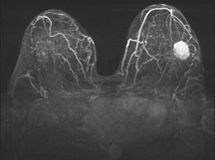

Mit der MR-Mammografie kann das Brustgewebe bis zur Brustwand und vorderen Achsel erfasst werden. Dabei werden die Brüste nicht komprimiert und verformt, was eine präzise Ortsbestimmung von Veränderungen in der Brust ermöglicht. Da das Brustgewebe in dünnen Schichten untersucht wird, ist die Diagnose nicht durch Überlagerungen beeinträchtigt. Während der Untersuchung wird über eine Nadel in einer Vene ein Kontrastmittel appliziert, wodurch die Durchblutung von Herdbefunden sichtbar gemacht wird. Dies ist für die Tumorerkennung von entscheidender Bedeutung. Bei vorhandenen Brustimplantaten können Defekte erkannt werden und die Region hinter den Implantaten beurteilt werden.

Für die Untersuchung werden zunächst Schnittbilder ohne Kontrastmittel angefertigt. Um die Lage und Unversehrtheit von vorhandenen Brustimplantaten zu überprüfen, werden spezielle Schichtführungen und Sequenzen verwendet. Anschließend wird das Kontrastmittel über die zuvor eingebrachte Nadel verabreicht und Schnittbilder nach Kontrastmittelgabe angefertigt. Insbesondere für die Erkennung von Brustkrebs ist der Einsatz von Kontrastmittel zwingend notwendig. Die gesamte Untersuchung dauert ca. 20 Minuten.